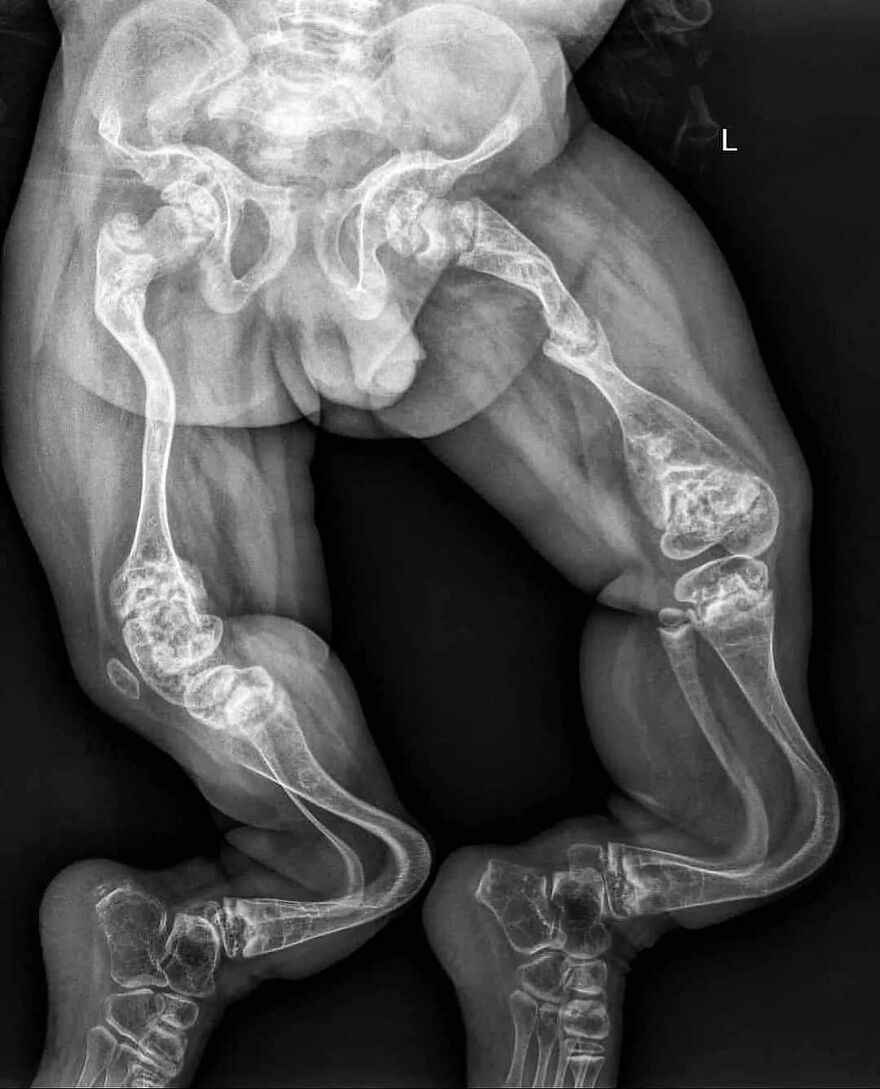

Foot binding (also known as Lotus foot) was the custom of applying tight binding to the feet of young girls to modify the shape and size of their feet

It was practised in China from the Song dynasty until the early 20th century, and bound feet were considered a status symbol as well as a mark of beauty

Foot binding limited the mobility of women, and resulted in lifelong disabilities for most of its subjects, although some women with bound feet working outdoors have also been reported

The age in which the binding happens differs in areas, but happend between 4 and 8 years old. The process takes about two years and is extremely painful: bones in the foot are broken, and replaced under the foot. All this time, girls must keep walking to put pressure on the bind foot, and achieve the ideal shape and length. 1 in 10 girls would die during the binding because of complications, and other complications happend quite regurlaly: not all binded woman could walk properly because of binding gone wrong. The ideal length of a bound foot would be around 7 cm. Kind of the size of a thumb. Without bound feet woman were unmarriable. Woman with unbound feet often became maids or worse. Source: my head, because of books I've read. Edit: grammar mistake